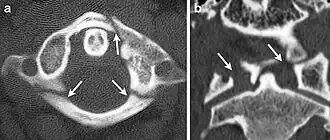

Detección radiográfica

En la tomografía computarizada o en la radiografía, puede visualizarse directamente una fractura cervical. Además, los signos indirectos de lesión de la columna vertebral son las incongruencias de las líneas cervicales, y/o el aumento del grosor del espacio prevertebral.[1]